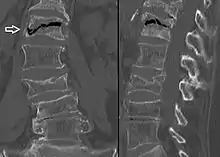

The intravertebral vacuum cleft sign (white arrow) is a sign of avascular necrosis. (Avascular necrosis of a vertebral body after a vertebral compression fracture is called Kümmel's disease.[12])